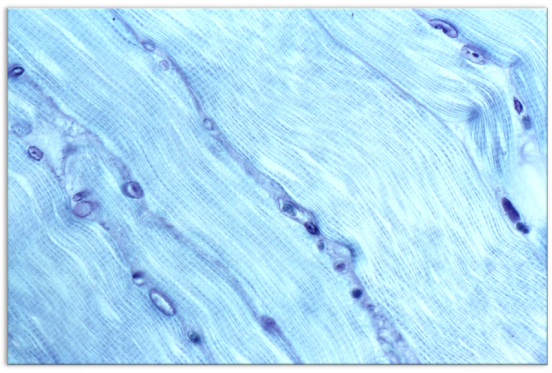

Additionally, we also have safety gloves in stock & ready to ship, alongside the Single XRF Standard for X-Ray Fluorescence Spectroscopy with a new, easy-to-use webpage that encompasses all of the available elements. Finally, our blog post for September is a technical paper using LR Gold.